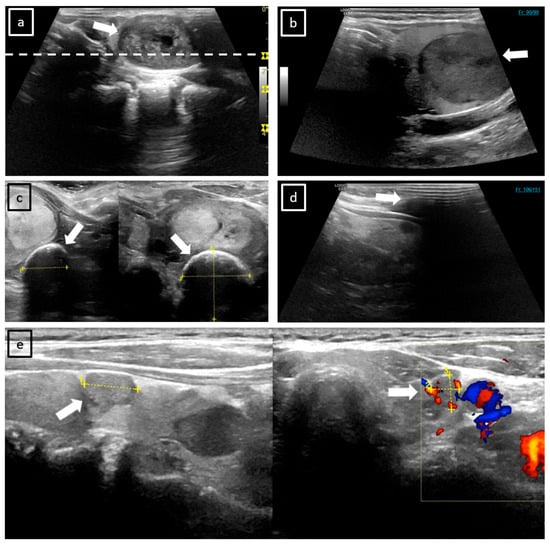

Figure 3. Examples of frequent ultrasound image artifacts. (a) The SIC of a left-sided TN (white arrow) in the sagittal plane. On the right side of the image, the depths of three foci are visible as yellow markers. The white dotted line indicates that only one of these foci lies within the TN, which may result in a reduction in image quality in the region of interest. (b) This illustration depicts a prevalent issue that manifests particularly in caudally localized TNs on CL. The TN is cut in the sagittal plane, as indicated by the white arrow. It is important to note that this TN has not been fully captured by the respective sagittal CL scan, as frame 90 of 90 is reached (numbers are displayed in the upper right corner). (c) TNs in the transverse and sagittal plane on SIC, with superimposed measurement lines (yellow markers). The assessment is hindered by extensive rim calcification at the top of the TN (marked by white arrows), which obscures its structural ultrasound features and impairs the evaluation of its size. (d) Acoustic shadowing (white arrow) of the primary components of the displayed CL capture is shown, likely attributable to an inadequate application of ultrasound gel. (e) The left part of this SIC shows the sagittal plane with measurement lines (yellow markers) superimposed upon the TN (white arrow). The right part of the image depicts additional Doppler visualization, which complicates the assessment (white arrow).

Cropped poles, breathing-related movements, and inadequate application of ultrasound gel (Figure 3) can also impair CL quality. In contrast, CL can effectively avoid acoustic shadowing by allowing the selection of unobscured frames. In the future, the quality of CL could be enhanced by implementing a more comprehensive training program for all physicians performing ultrasound procedures with automated artifact detection and correction algorithms. Physician training programs may be based on previously acquired scans, thereby facilitating the identification of prevalent issues and ensuring a targeted, effective resolution. To ensure the integrity of the data, personnel could be requested to undertake a direct examination of the recorded CL to identify artifacts and be instructed to re-initiate the acquisition process if necessary. In cases where patients present special anatomical features, such as a short neck or a prominent larynx, it is imperative to ensure the application of a sufficient amount of ultrasound gel. Furthermore, the proper positioning of the head and neck region is crucial for acquiring high-quality ultrasound data.